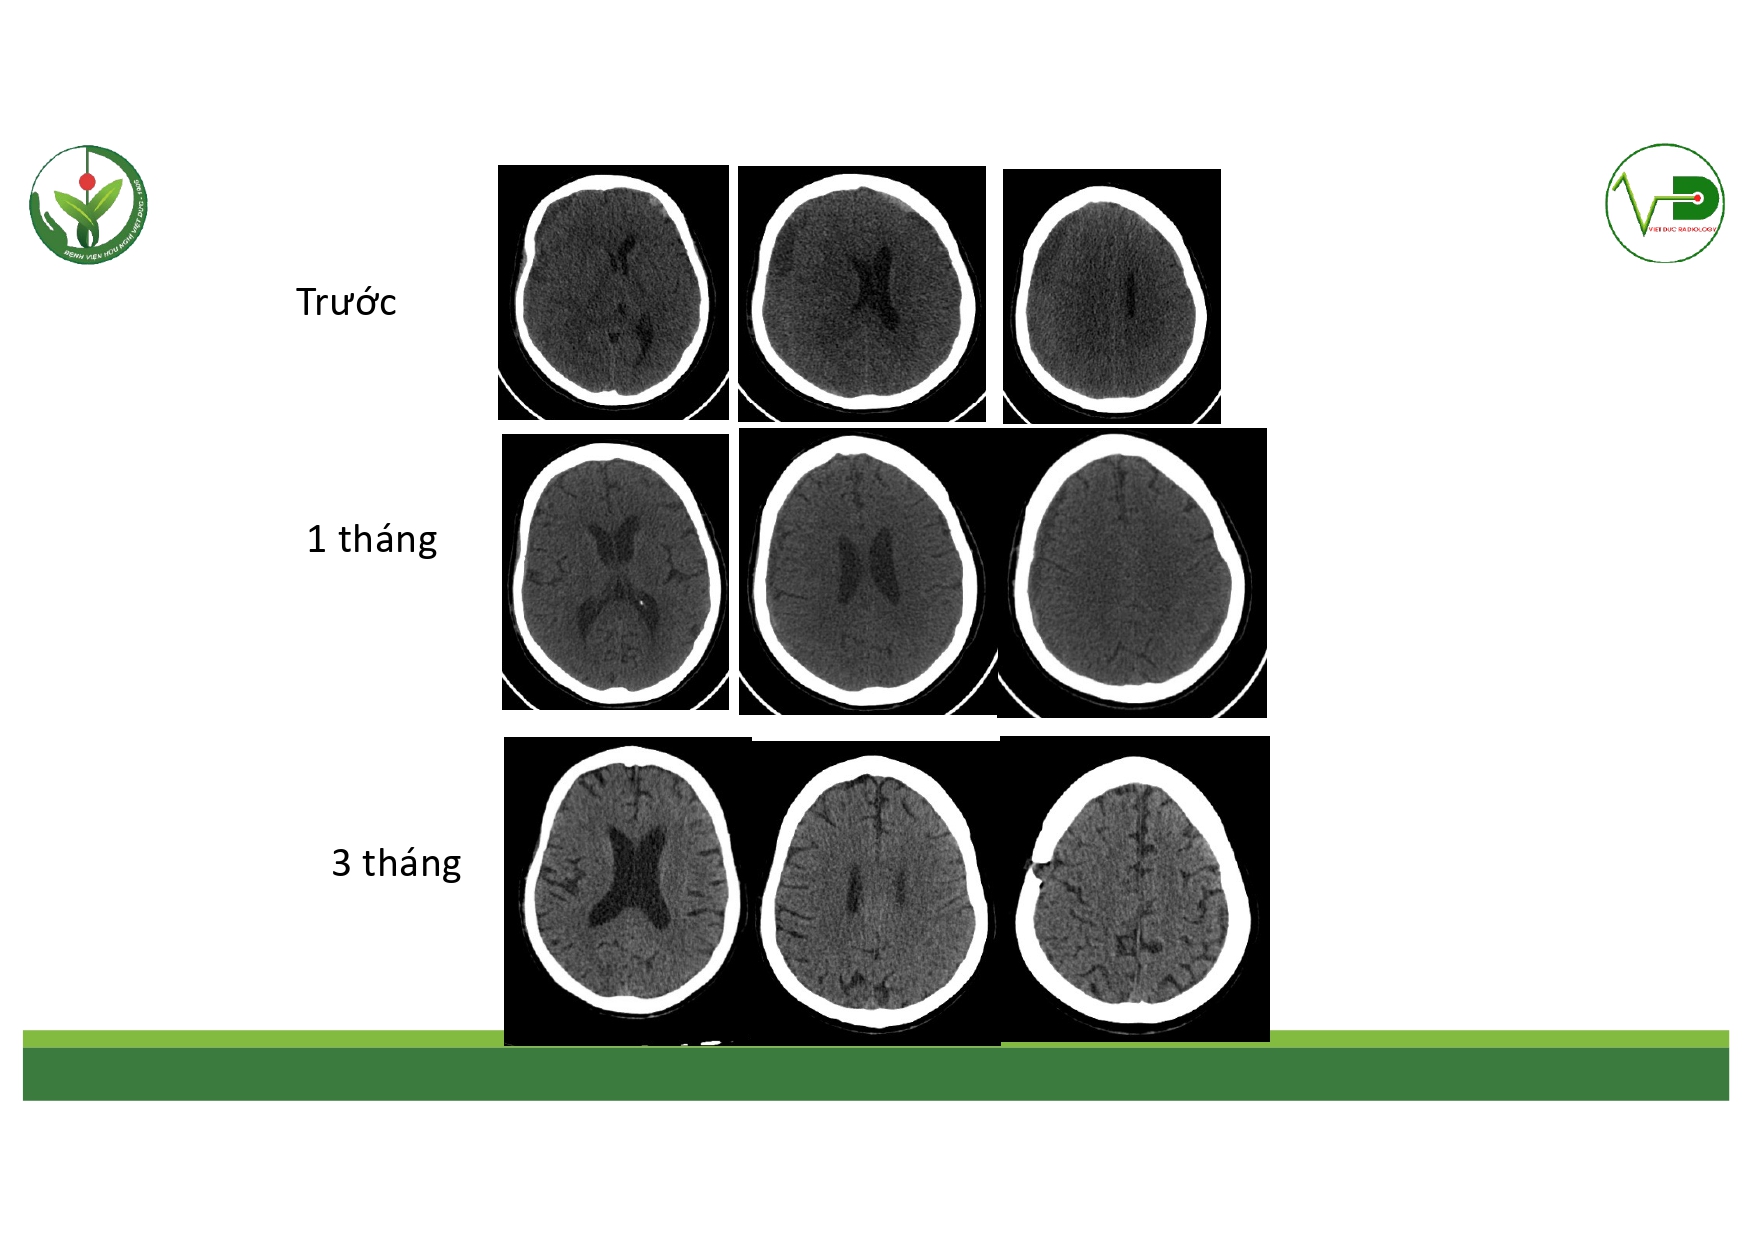

| 14:10 - 15:10 | DEBATE 2 | Recurrent chronic subdural hematoma– surgical or endovascular intervention? Surgical: Assoc. Prof. Duong Dai Ha Endovascular: Assoc. Prof. Le Thanh Dung | Moderator: Prof. Christian Matula Assoc. Prof. Duong Dai Ha | |